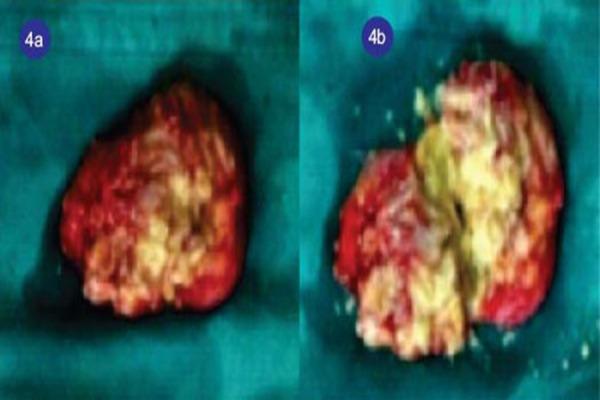

A 42-year-old female patient is presented with golf ball sized painless swellings in the posterior aspect of her elbows. Elbow joints were clinically normal except for restriction of terminal flexion. X-ray showed mild erosion at the tip of olecranon. Excision biopsy of the swelling showed positive birefringent calcium pyrophosphate dehydrate crystals on the inner wall of the specimen on polarized light microscopy.

一名42岁女性患者,双侧肘部后方出现高尔夫球大小的无痛性肿胀。除终末屈曲受限外,肘关节临床检查正常。X线显示鹰嘴尖端轻度侵蚀。肿胀部位的切除活检在偏振光显微镜下显示标本内壁有阳性双折射焦磷酸钙脱水晶体。